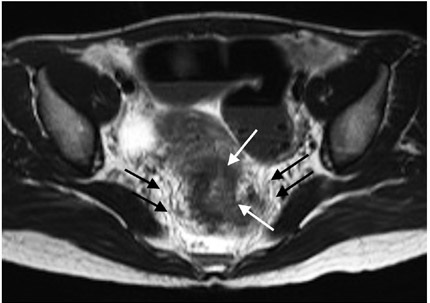

Los elementos que deben ser valorados en una resonancia magnética para cáncer rectal primario son el estadio, la profundidad de la invasión más allá de la muscular propia y la relación del tumor con la fascia mesorrectal (figura 1), la fascia presacra (figura 2), el esfínter anal y las paredes de la pelvis (15).

La estadificación del tumor depende directamente de su relación con la capa muscular propia y de la invasión con los órganos adyacentes (8). Un tumor T1 es aquel que se encuentra confinado a la mucosa, un tumor T2 es el que se extiende hasta la muscular propia (figura 3), un tumor T3 invade y se extiende más allá de la muscular propia (T3 temprano menor de 5 mm o T3 avanzado mayor de 5 mm) (figuras 4 y 5) y un tumor T4 es aquel que invade los órganos pélvicos (figura 6) (15). Los vasos pélvicos, la fascia parietal pélvica y la fascia mesorrectal no son considerados órganos (8).

La fascia mesorrectal es un punto de referencia anatómica para la evaluación diagnóstica de la extensión tumoral (33,34); este es el factor más importante en cuanto al pronóstico (8) ya que el compromiso de la fascia mesorrectal aumenta el riesgo de recurrencia local y a distancia (8). La fascia mesorrectal corresponde a la capa visceral de la fascia intrapélvica (15). Compone una unidad anatómica diferente al rodear el recto y contener la grasa mesorrectal, ganglios y vasos linfáticos (15). En imágenes de alta definición con información T2 se visualiza como una imagen hipointensa lateral al recto (figura 1) (15).

Se localiza desde el aspecto superior de la vejiga hasta el aspecto anterior del recto, formando el saco rectovesical (15). En imágenes de alta definición con información T2 se visualiza como una imagen hipointensa en forma de “V” en imágenes axiales (15). El compromiso de esta fascia por parte del tumor hace que se estadifique como un estadio T4a (15).